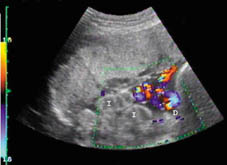

Corte transversal de abdomen. Gracias al Doppler color, podemos observar en este caso, claramente, que el defecto (D) se sitúa a la izquierda de la inserción del cordón umbilical (presentación cefálica).